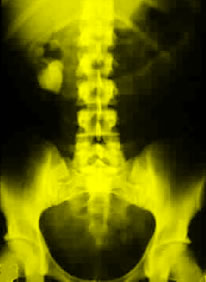

Kidney stones are a major cause of illness, according to background information in the article. The lifetime prevalence of kidney stones is approximately 10 percent in men and 5 percent in women, and more than $2 billion is spent on treatment each year. Researchers believe that larger body size results in increased urinary excretion of calcium and uric acid, thereby increasing the risk for calcium-containing kidney stones. It has been unclear if obesity increases the risk of stone formation, and it has not been known if weight gain influences risk.

The researchers found that after adjusting for age, dietary factors, fluid intake, and thiazide (diuretics) use, men weighing more than 220 lb. had a 44 percent increased risk for the development of kidney stones than men weighing less than 150 lb. For these weight categories, older women had a 89 percent increased risk; younger women, a 92 percent increased risk. Men who gained more than 35 lb. since age 21 years had a 39 percent increased risk for kidney stones, compared to men whose weight did not change. With similar weight gain, older women had a 70 percent higher risk for the development of kidney stones; younger women, an 82 percent increased risk. The researchers also found that higher BMIs and waist sizes were associated with a higher risk for kidney stones.